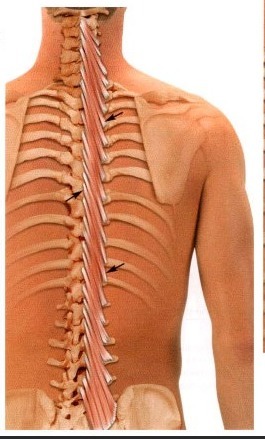

Глубокие мышцы спины представлены тремя слоями. Конкретно вышеперечисленные функции выполняют сразу несколько мышц:

1. Мышца,выпрямляющая позвоночник.Тянется она от крестца до основания черепа,несмотря на то,что в верхней части туловища распадается на три мышечных пучка. Кроме разгибания тела данная мышца выполняет ещё и функцию удержания туловища в вертикальном положении.

2. Поперечно-остистая мышца,составляющая средний слой. Крепится к поперечным и остистым отросткам позвонков,состоит из нескольких пучков,которые совместно тянутся по всей длине позвоночника,выполняет ту же функцию разгибания позвоночника и его вращения.

(Картинки даны последовательно)